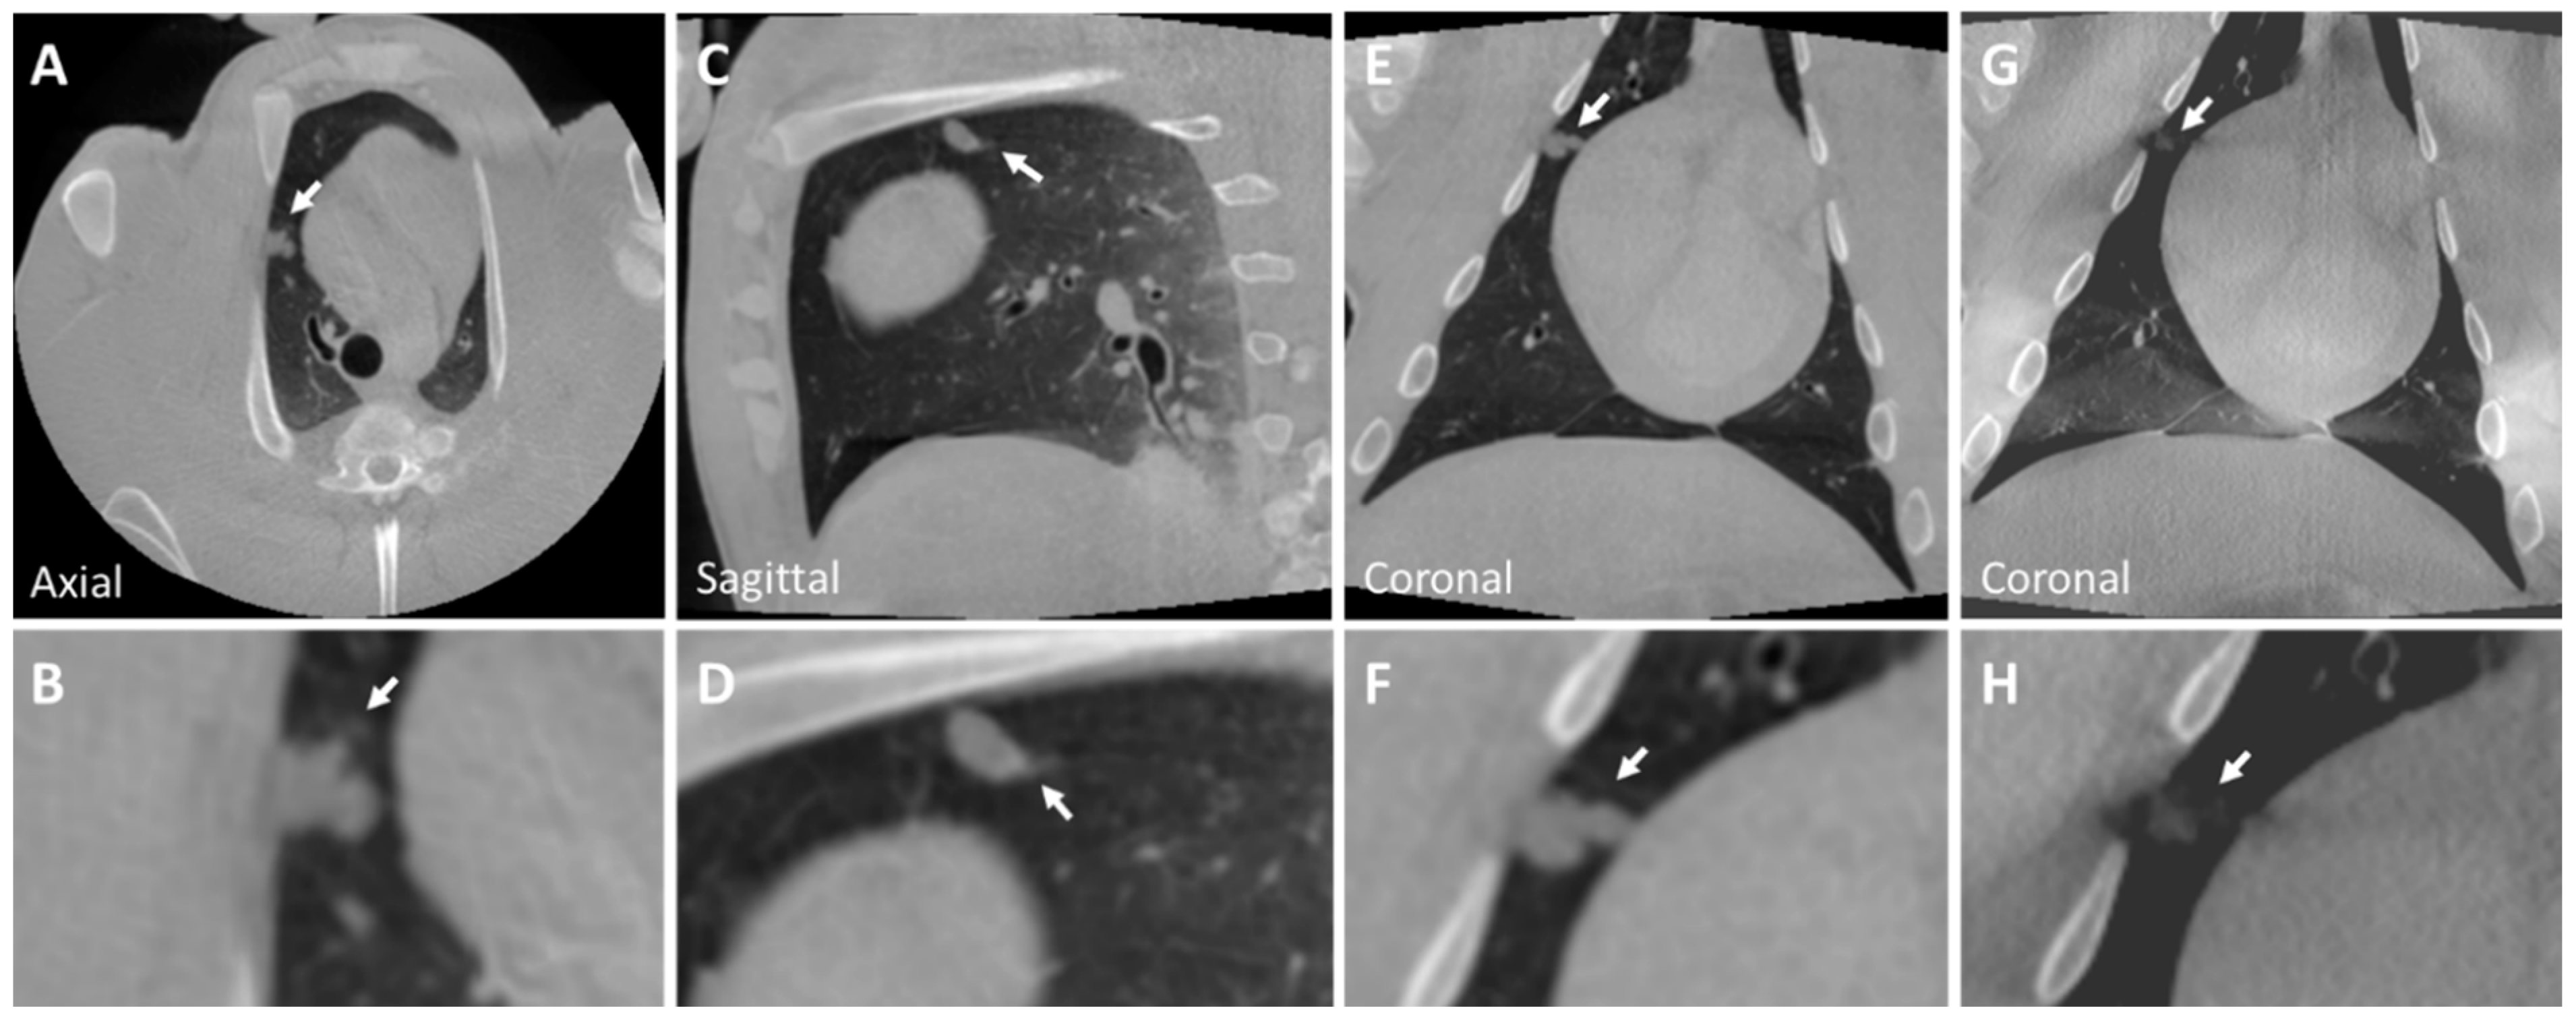

3.1. Ex Vivo Swine Lungs

3.2. Post-Mortem Swine Lungs